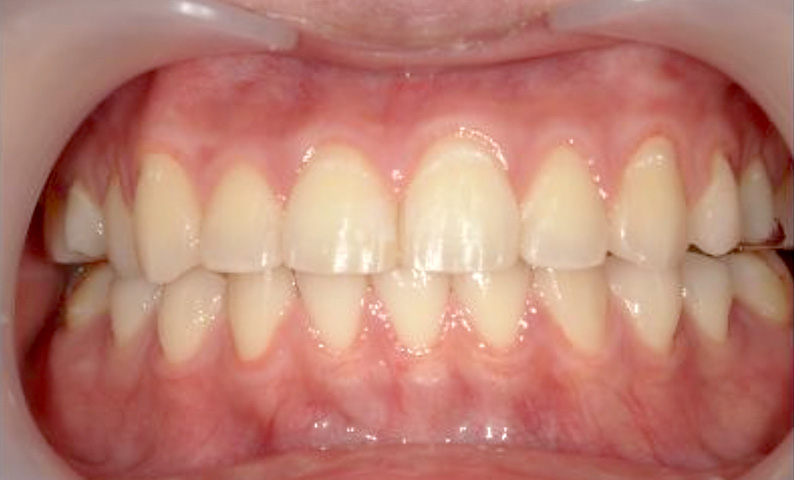

症例_025 上下顎の部分矯正

治療期間:13ヶ月金額:51万円+税女性前歯のガタガタ出っ歯

| Before | After |

|---|---|

|